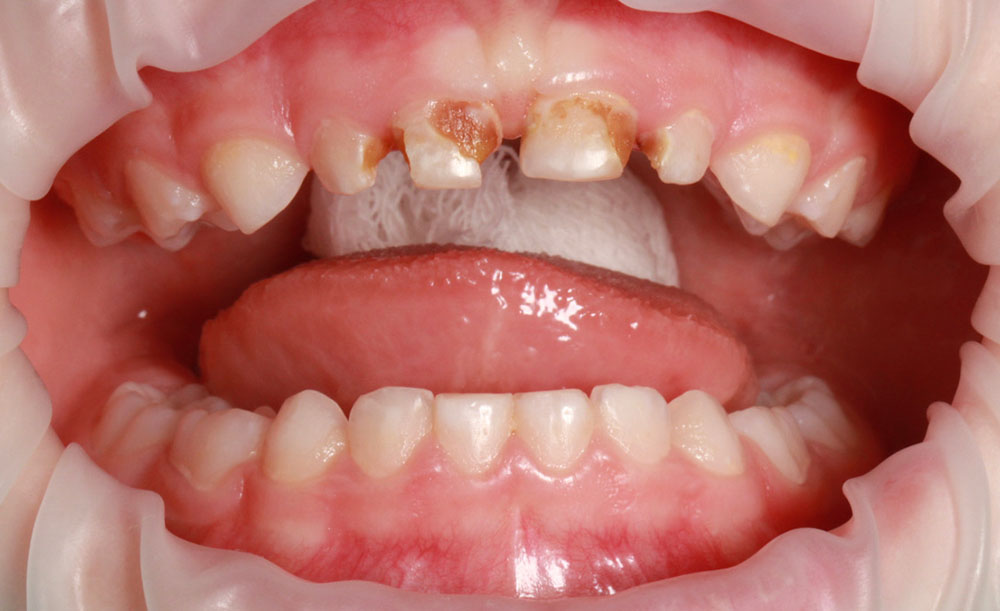

Лечение кариеса зубов у детей

При лечении кариеса у детей применяются мягкие и щадящие способы. Нашим приоритетом является комфорт маленького пациента.

Приступая к лечению кариеса у детей, врачу необходимо убедиться, что ребенок доверяет ему. Мы против удержания детей во время лечения. Лечение проводится в полном взаимопонимании. Используются только специальные материалы, одобренные для лечения детей, производства Германия, Швейцария, Япония.

Всем известен звук стоматологической машины, даже взрослым непросто переносить его специфичный жужжащий тон, а детям он нравится еще меньше. Поэтому наши врачи минимально используют бормашину и стараются убрать пораженные ткани из молочных зубов с помощью специальных инструментов.